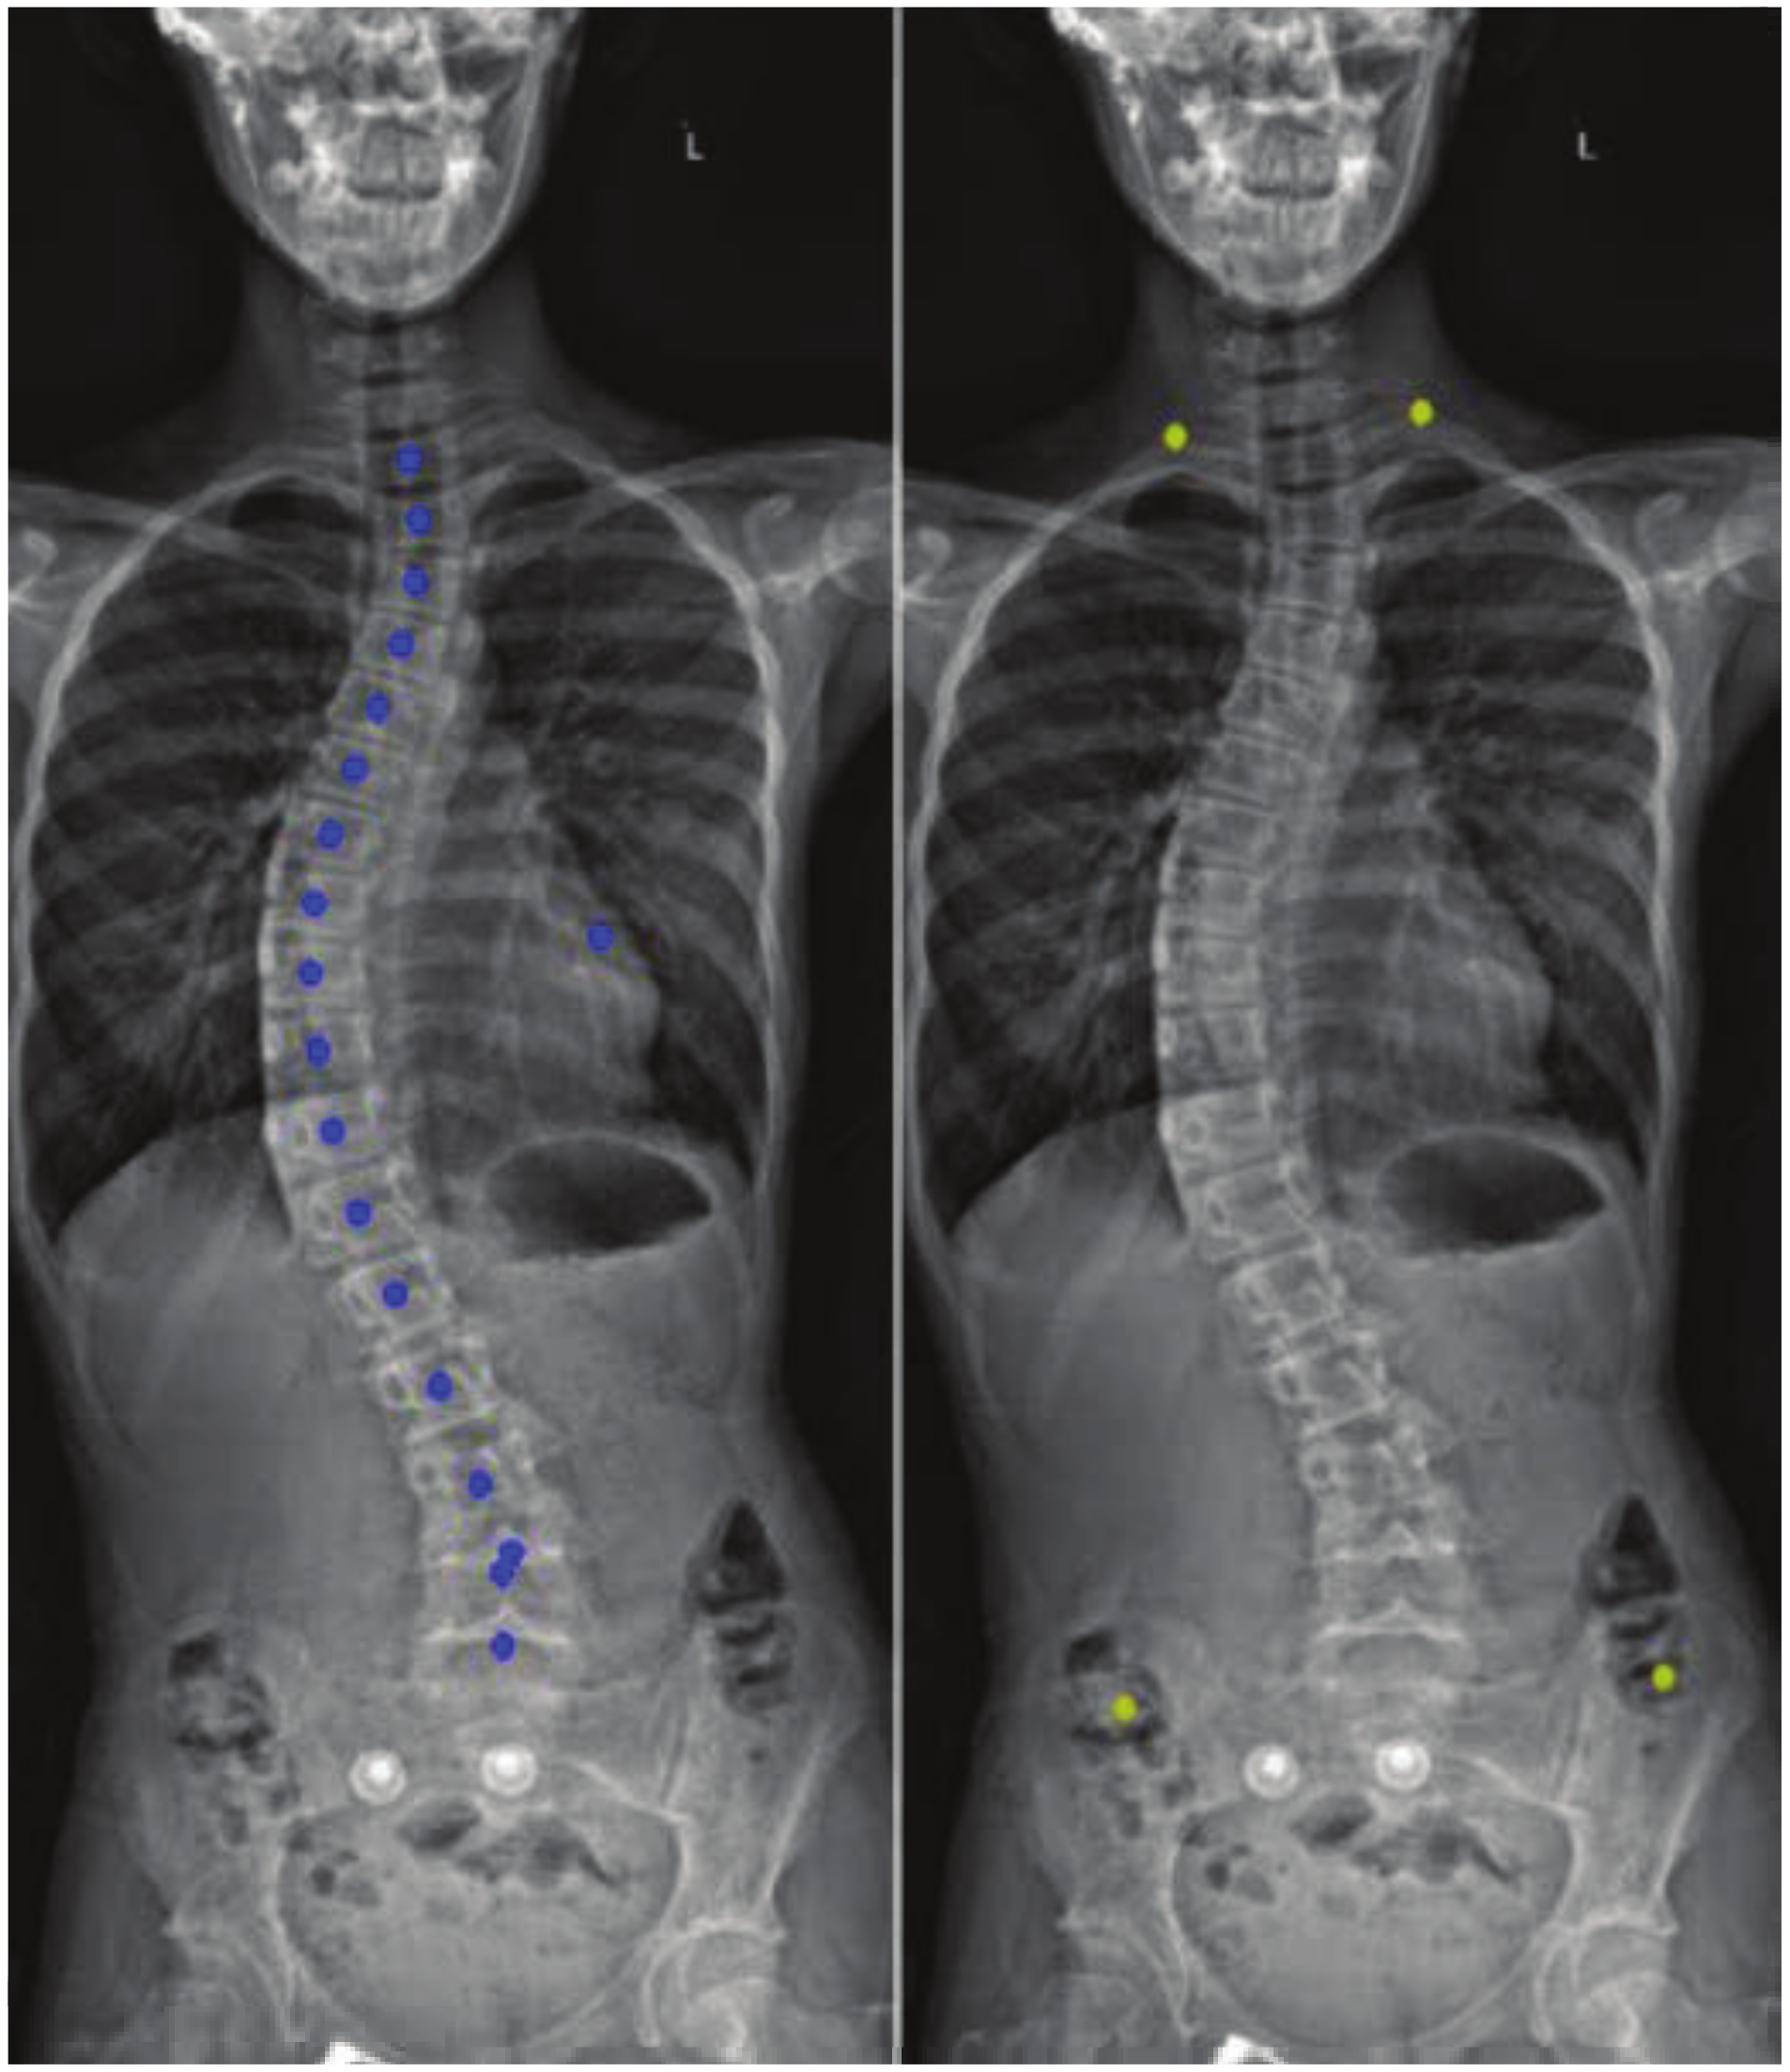

Vertebral Center Points Locating and Cobb Angle Measurement Based on Deep Learning

2. Manual Measurement of Scoliosis

3. Materials and Methods

3.4.2. Spine Curve Fitting and Cobb Angle Calculation